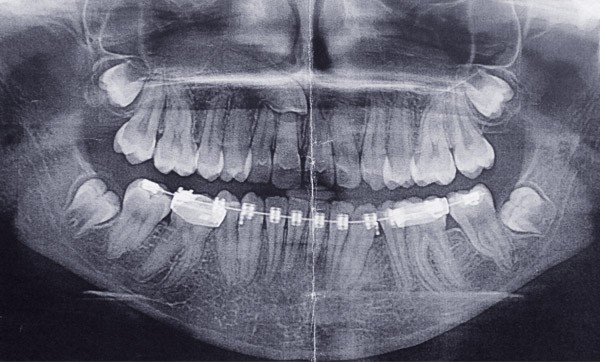

Information dentaire

Les dents incluses, dont la prévalence est estimée entre 8 et 38%, nécessitent une prise en charge pluridisciplinaire. Leur présence peut provoquer des complications justifiant leur extraction. Il est essentiel de diagnostiquer précocement une dent incluse afin d’optimiser les résultats de la prise en charge visant à favoriser l’éruption de la dent et afin d’éviter les risques associés à l’inclusion. La conduite à tenir face à une dent incluse dépend de la dent incluse, des dents environnantes, mais également du patient. Il est important de connaître les indications et les principes de base de la technique chirurgicale des extractions de dents incluses pour préserver au maximum les tissus et dents environnants. L’article traite des extractions des dents incluses, hormis les dents de sagesse.

Le choix de traitement d’une dent incluse va dépendre de la morphologie et du pronostic de la dent incluse, du pronostic des autres dents du patient et, surtout, des facteurs suivants : phénomènes pathologiques ou complications associés, l’âge et la coopération du patient, et la localisation de l’apex de la dent incluse.

Dans le cas de dents incluses multiples, une prise en charge méticuleuse doit être programmée pour guider autant de dents possibles vers leur éruption [2]. Cependant en cas d’échec, l’extraction des dents incluses est parfois nécessaire.